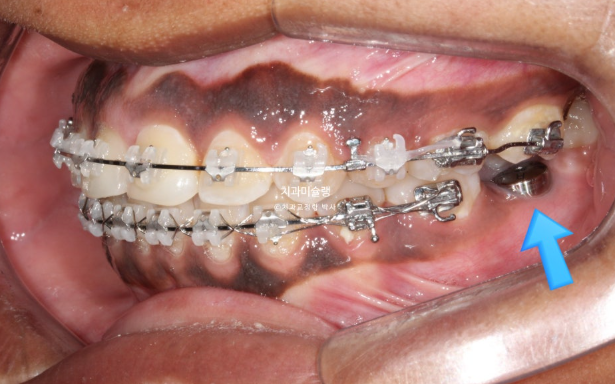

In the area of the missing mandibular molar, the site had been left untreated for a long period. As a result, the opposing tooth (indicated by the blue arrow) had supra-erupted.

For proper implant placement, this opposing tooth needs to be intruded through orthodontic treatment.

The treatment plan involves first closing the extraction spaces by retracting the protruded anterior teeth, followed by sequential intrusion of the supra-erupted molar.

At this stage, the implant fixture was first placed in the mandibular posterior region, followed by intrusion of the supra-erupted opposing tooth.

For effective intrusion, a temporary orthodontic mini-screw was placed in the palate.